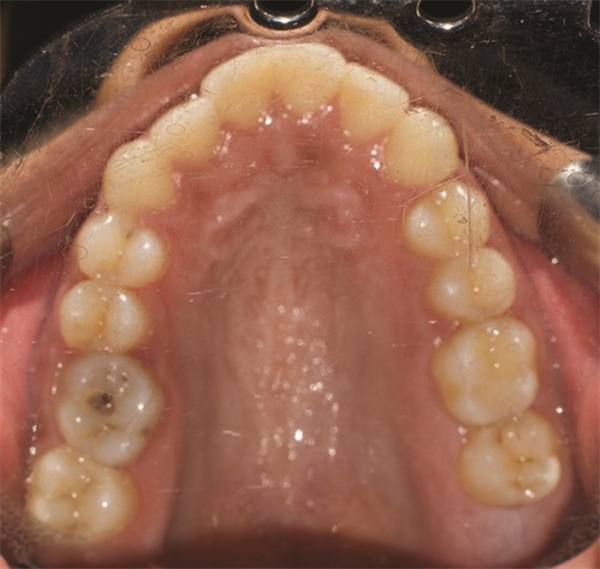

The diagnostic findings told a more complicated story. The patient presented with a skeletal Class II relationship, bilateral Class I molar and canine relationships, collapsed arches, and proclined incisors in both arches. Both midlines were shifted to the right. She also exhibited crossbite of the upper right first molar and upper right lateral incisor, a discrepancy between centric relation and centric occlusion, and a noticeable cant in the lower anterior segment. Her dental history included previous extractions of the upper right third molar and upper left second molar (Figs. 1–12).

Fig. 2